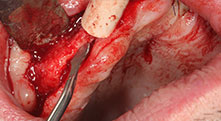

Würden Sie uns kurz beschreiben, wie Sie zum Beispiel beim Mobilisieren von Knochenblöcken für Transplantationen vorgehen?

Bratu: Wir bevorzugen Knochenentnahmen von der Linea obliqua externa des posterioren Unterkiefers, nicht aus der interforaminalen Region. Nach der Weichgewebsinzision verwenden wir die neuen Sägen, um den Umfang der Knochenentnahme zu definieren. Wir erledigen damit in fast 80 Prozent der Fälle auch die gesamte Präparation. Zusätzlich verwenden wir eventuell andere Piezo-Instrumente und zuletzt einen Meißel, um den Block zu mobilisieren. Das ist für uns eine sehr effektive Operationstechnik.